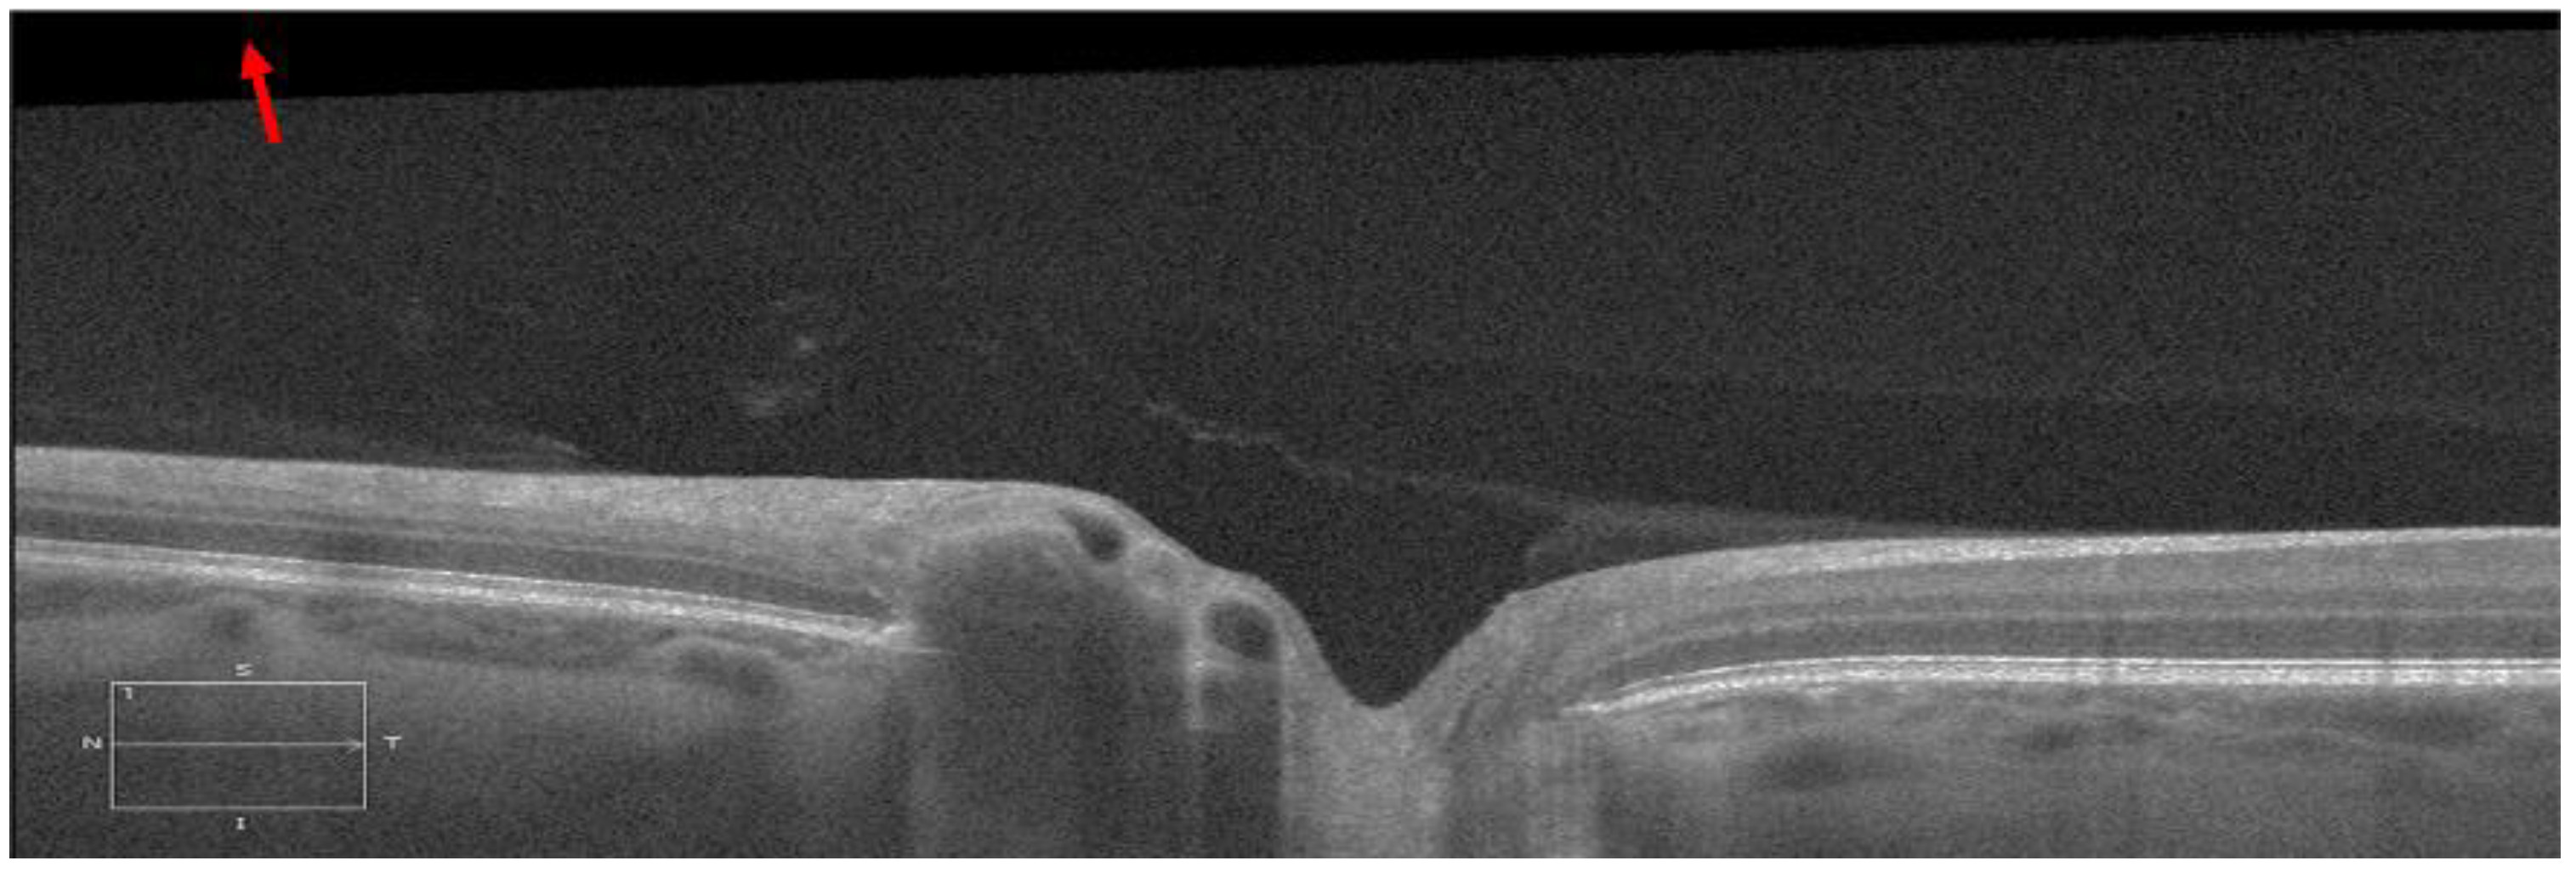

The OCT imaging was performed for both eyes immediately before and 30 min after LP, using Cirrus HD-OCT (Carl Zeiss Meditec Inc, USA). The radial scan protocol consisted of 12 cross-sectional scans (also referred to as B-scan) centered on the ONH (Figure 1A). For image radial position consistency, the B-scans acquired before LP were used as the reference for the B-scans acquisitions after LP. Each B-scan was exported from the OCT machine in TIFF format with a size of 938 × 625 pixels (3 × 2 mm) and an aspect ratio of 0.5 (Figure 1B). All B-scans analyzed in this study had an image quality of 7 or higher. All B-scans were then converted to their anatomically correct size of 1876 × 625 (6 × 2 mm) by stretching the image horizontally with a factor of 2 (Figure 1C). The pixel size in the scan with an aspect ratio of 1 was 3.2 µm.

Figure 1. (A) The radial scan protocol consisted of 12 radial B-scans. Each red arrow line indicates one radial scan, with the arrow indicating the scanning direction was from the left to right in each B-scan. (B) The original B-scan with a size of 938 × 625 pixel (3 × 2 mm) and an aspect ratio of 0.5. (C) Each B-scan was converted to its anatomically correct size of 1876 × 625 pixel (6 × 2 mm) with an aspect ratio of 1.

The ppRPE/BM layer in the OCT images was automatically segmented using OCTSEG (Version 0.4, Pattern Recognition Lab, Friedrich-Alexander University) [17]. This open-source segmentation tool has been applied to segment the continuous retinal layers [18,19,20]. However, it was difficult to segment the discontinuous retina layer in the ONH region. Hence, we divided the B-scans into three zones: left, mid, and right with size of 450 × 625 pixel, 976 × 625 pixel, and 450 × 625 pixel, respectively (Figure 2 Top). Both the left and right zones with continuous retina layers were used for the ppRPE/BM layer segmentation. The automatic segmentation results were reviewed by two trained graders independently. If the ppRPE/BM layer was not correctly segmented, manual correction was applied by experienced graders to repaint the segmented layer.

Figure 2. Each B-scan was divided into three zones as marked by two red vertical lines and only the left and right zones were segmented (Top). The segmented ppRPE/BM layers were highlighted in blue color with an angle γ relative to the X-axis. (A,C). The corresponding linear regression models of the segmented ppRPE/BM layers in the left and right zones (B,D).